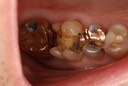

Kyle Chock #18 pre-op

Kyle Chock #18 amalgam removal